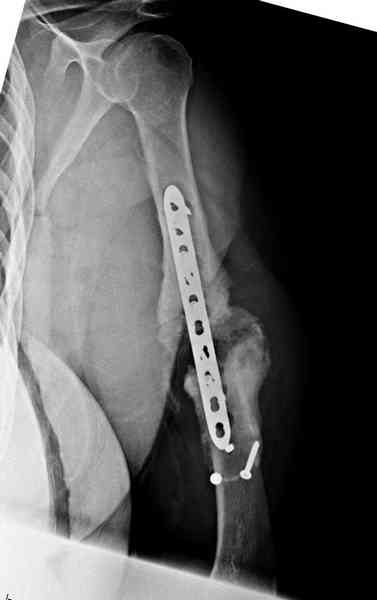

Первичную пластину убрали недели 6 назад из переднего оригинального доступа, и из-за подозрительности тканей вокруг пластины, решили провести реконструкцию поэтапно.

После промывки и дебридмента для уверенности уложили антибиотический цемент. Культура из раны в последующем была отрицательная.

Хотя сам не стороннник применения более массивных

имплантов для плеча, но для этого случая сделали

исключение. На снимке 4А диаметр мягких ткани около 20 см, при весе больной более 135 кг, и также выступление Андрея Волны подстегнуло к применению более массивной 4.5 мм локинг пластины.